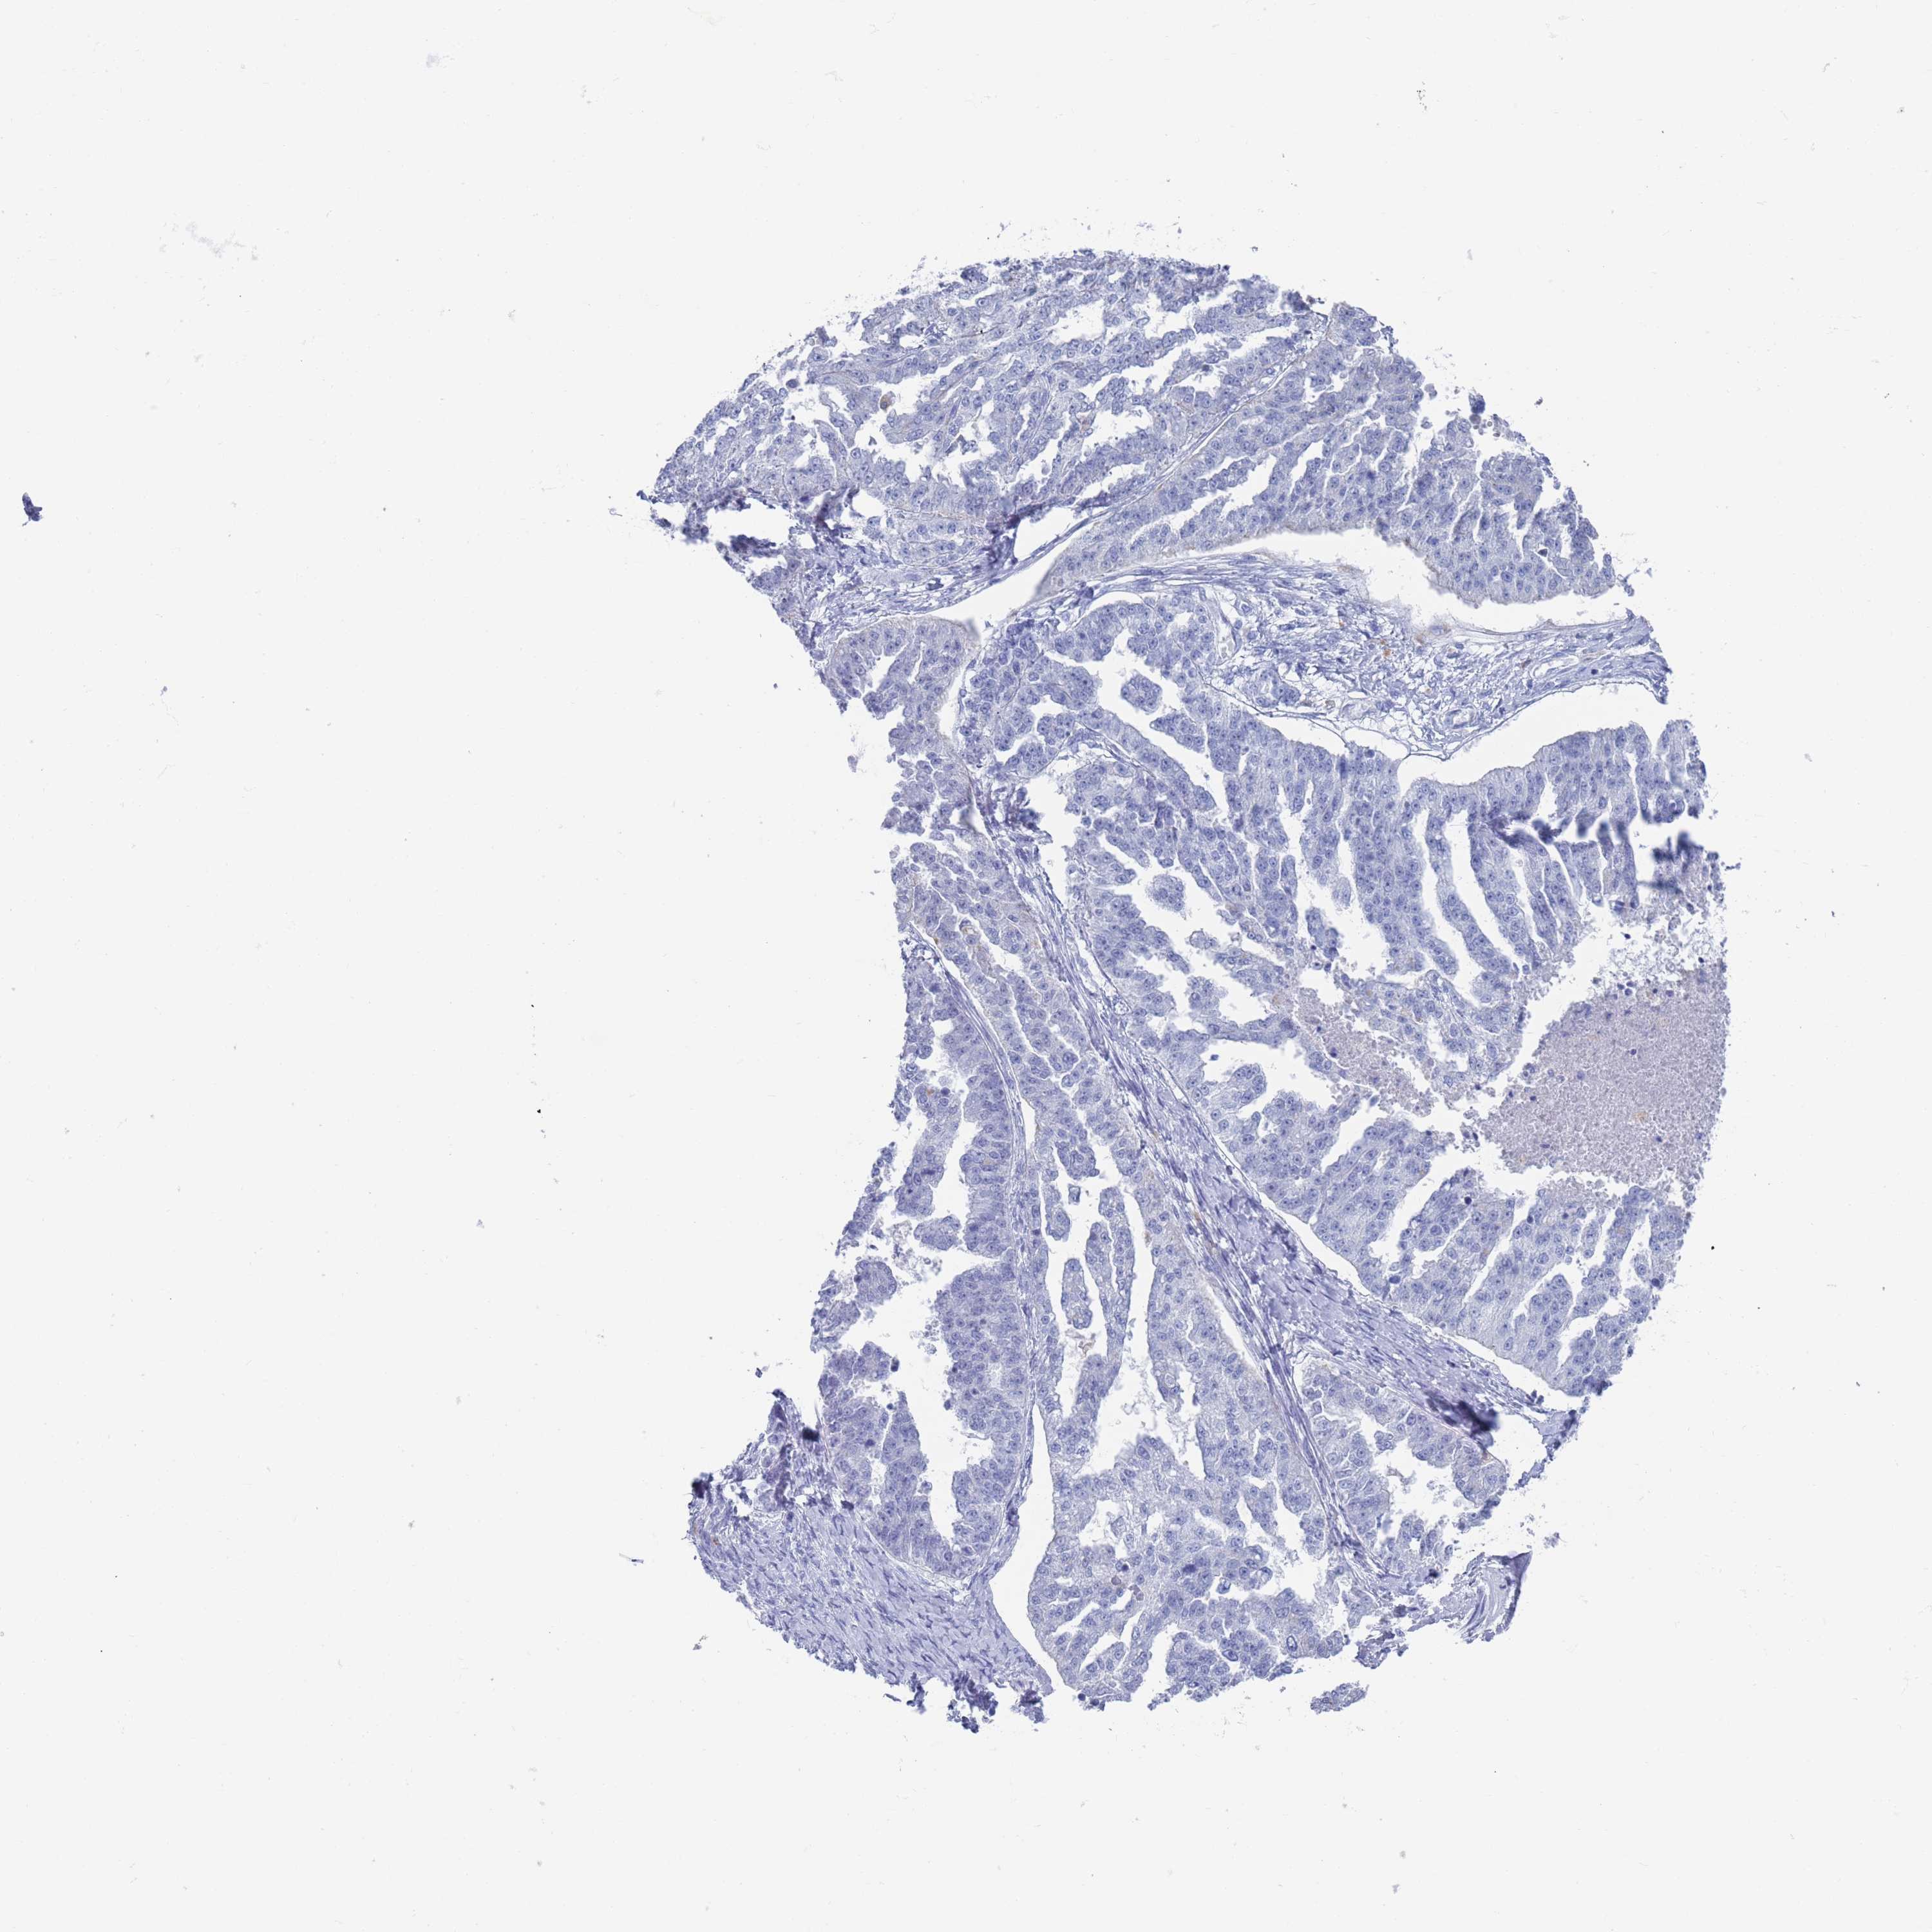

OVARIAN CANCER - Protein expressioni

A mouse-over function shows sample information and annotation data. Click on an image to view it in a full screen mode. Samples can be filtered based on level of antibody staining by selecting one or several of the following categories: high, medium, low and not detected. The assay and annotation is described here.

Note that samples used for immunohistochemistry by the Human Protein Atlas do not correspond to samples in the TCGA dataset.

Antibody stainingi

Antibody staining in the annotated cell types in the current human tissue is reported as not detected, low, medium, or high, based on conventional immunohistochemistry profiling in selected tissues. This score is based on the combination of the staining intensity and fraction of stained cells.

Each image is clickable and will lead to virtual microscopy that enables deeper exploration of all samples and also displays staining intensity scores, fraction scores and subcellular localization as well as patient and tissue information for each sample.

Antibody HPA046542

Antibody HPA056371

Staining

High

Medium

Low

Not detected

Intensity

Strong

Moderate

Weak

Negative

Quantity

>75%

75%-25%

<25%

None

Location

Nuclear

Cytoplasmic/membranous

Cytoplasmic/membranous,nuclear

Cystadenocarcinoma, serous, NOS

Carcinoma, NOS

Cystadenocarcinoma, mucinous, NOS

Carcinoma, endometroid